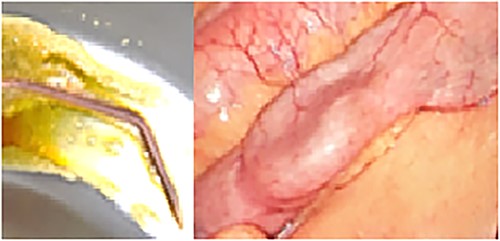

The patient was referred for laparoscopic revision surgery with conversion to RYGB (Fig. 3). In the postoperative period, a torpid evolution included vomiting on various occasions, as well as the detection of ascaris on one occasion. A new upper GI endoscopy showed evidence of permeable gastrojejunal anastomosis and acute inflammatory changes (Fig. 4), and the patient received antiparasitic treatment. Because of persistent symptoms of obstruction, a new surgical intervention was performed, which showed the presence of ascaris in the entero-enteric anastomosis causing its obstruction (Fig. 5). A new anastomosis was performed at a distance of 30 cm from the obstruction (Fig. 6). After the patient showed improvement and tolerated a liquid diet, she received treatment for ascaris and was discharged with good evolution.

Diagram showing the construction of a new entero-enteric anastomosis.

Certain final details of the technique are essential to ensure the success of these procedures [1]. In the present case, the patient showed oral intolerance and evidence of malnutrition, which led us to consider revision surgery. Conversion to RYGB was performed in an emergency context in a safe and effective manner. In the postoperative period, we found obstruction of the entero-enteric anastomosis caused by a parasite, which was removed and the anastomosis was repaired, showing adequate postoperative evolution.